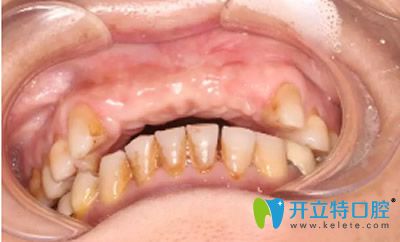

成都新橋口腔種植牙齒前

60?70?錯(cuò)!路女士今年43歲,曾因意外折斷了5顆上前牙,又因?yàn)椴唤?jīng)常潔牙的原因,導(dǎo)致了滿口都是黃牙。這樣的牙齒,怎敢在別人面前自信講話和微笑嗎? 所以她一直戴著活動(dòng)假牙。時(shí)間久了,假牙的基托和卡環(huán)對(duì)進(jìn)食和生活影響很大,只好來(lái)新橋口腔尋求更好的修復(fù)辦法。